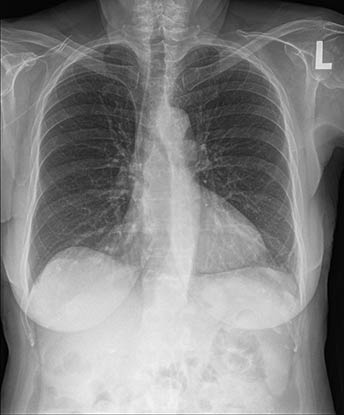

骨抑制利用人工智能创建伴随影像并抑制骨骼的出现,以增强软组织的可视化,同时不需要患者进行额外的暴露。这有助于提高病理学评估的临床信心。